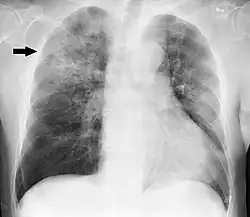

A chest radiograph is frequently used in diagnosis.[23] In people with mild disease, imaging is needed only in those with potential complications, those not having improved with treatment, or those in which the cause is uncertain.[23][69] If a person is sufficiently sick to require hospitalization, a chest radiograph is recommended.[69] Findings do not always match the severity of disease and do not reliably separate between bacterial and viral infection.[23]

X-ray presentations of pneumonia may be classified as lobar pneumonia, bronchopneumonia, lobular pneumonia, and interstitial pneumonia.[75] Bacterial, community-acquired pneumonia classically show lung consolidation of one lung segmental lobe, which is known as lobar pneumonia.[42] However, findings may vary, and other patterns are common in other types of pneumonia.[42] Aspiration pneumonia may present with bilateral opacities primarily in the bases of the lungs and on the right side.[42] Radiographs of viral pneumonia may appear normal, appear hyper-inflated, have bilateral patchy areas, or present similar to bacterial pneumonia with lobar consolidation.[42] Radiologic findings may not be present in the early stages of the disease, especially in the presence of dehydration, or may be difficult to interpret in the obese or those with a history of lung disease.[24] Complications such as pleural effusion may also be found on chest radiographs. Laterolateral chest radiographs can increase the diagnostic accuracy of lung consolidation and pleural effusion.[41]

A CT scan can give additional information in indeterminate cases[42] and provide more details in those with an unclear chest radiograph (for example occult pneumonia in chronic obstructive pulmonary disease). They can be used to exclude pulmonary embolism and fungal pneumonia, and detect lung abscesses in those who are not responding to treatments.[41] However, CT scans are more expensive, have a higher dose of radiation, and cannot be done at bedside.[41]